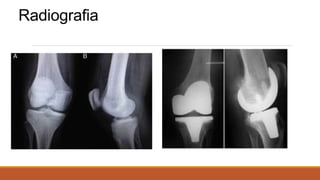

Avaliação de Radiografias do

Sistema Musculoesquelético

1- Identificar os aspectos técnicos da radiografia:

Posicionamento no negatoscópio: A radiografia é colocada

com a etiqueta à esquerda do observador.

Eventualmente o técnico em radiologia pode acrescentar o

sinal “D” ou “R” para facilitar a identificação do lado direito e

“E” ou “L” para o esquerdo.

Avaliação de Radiografias do Sistema

Musculoesquelético

Região examinada: Geralmente descrevemos o osso

(fêmur, tíbia, radio...), a articulação (quadril, joelho,

cotovelo...) ou a região (bacia, coluna cervical...).

- Incidência: o exame de cada região deve ser realizada em

pelo menos duas incidências, preferencialmente

anteroposterior e perfil (AP + P). Outras: oblíquas e axiais.

-Exames especiais: radiografias panorâmicas e

escanometria.

2- Identificar os aspectos gerais do exame:

Identificar o que mais chama atenção na radiografia.

Em sequência observamos os seguintes parâmetros:

a) Contorno ósseo,

b) Formato do osso,

c) Textura do osso

d) Partes moles.

3-Identificar as particularidades das alterações encontradas:

Aspectos específicos

Alteração ou lesão significativa: caracterizar as

particularidades desta lesão e definir o diagnóstico.

Onde está a lesão?

Qual o tamanho da lesão?

O que a lesão está produzindo no osso?

Qual a resposta do osso?

Há lesão do córtex?

Quais as características da matriz da lesão?

Há massa de partes moles?